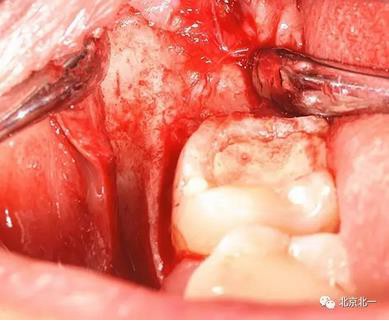

圖六:切開翻瓣, 看見骨面清晰,未見智齒

圖七:去骨后看不見牙齒位置方向。顏色無法區(qū)分,拍片確認一下剛才去骨的以及截的冠就是智齒。

圖八:把牙根優(yōu)先取出后還是看不見牙冠在哪里,實在貼的神經(jīng)管太近, 只能再次拍一個cbct確認。

圖十:實際情況:看到么在第二磨牙頰側接近近中區(qū)域。關鍵牙顏色和骨顏色一致, 只有牙冠部分是白色能看出來, 但是它卻深深的把頭埋下。